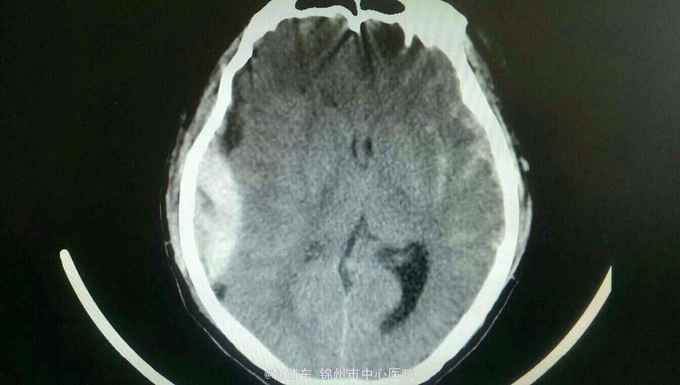

患者以车祸致头部外伤后意识不清两个小时为主诉入院。患者于入院两个小时前被汽车撞倒,伤及头部。伤后患者意识不清,恶心并呕吐数次,伤后无四肢抽搐。急诊以硬膜外血肿收入院。

中度昏迷状态,无语言,刺激后右侧肢体可动,左侧肢体不动。右颞头皮肿胀,双侧瞳孔不等大,右侧瞳孔直径5.0毫米,光反射无,左侧瞳孔直径3.0毫米,光反射迟钝。颈软,左侧肢体不动,右侧肢体少动。左侧病理反射阳性。头部ct如下。

诊断:脑疝 急性硬膜外血肿 脑挫裂伤 颅骨骨折 入院后完善术前准备,急诊行去骨瓣硬膜外血肿清除术。术中见骨折线,清除血肿,悬吊硬膜。术后复查ct提示对侧脑挫裂伤增大,伴水肿,暂不需要手术。降颅压治疗,密切观察病情变化。